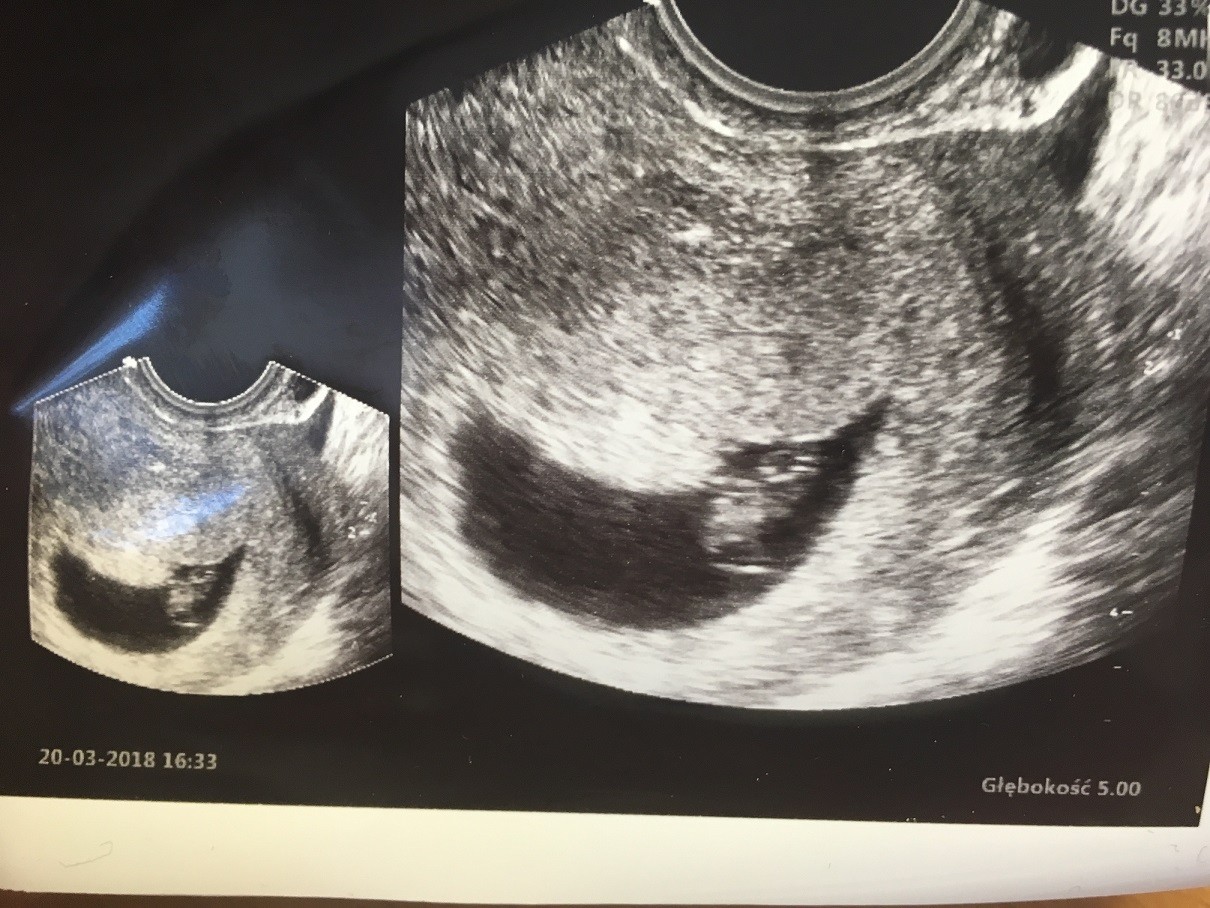

Ja po wizycie. Wizyta okropna. Dobrze, że idę tam tylko raz. Nie dała mi zdjęcia z usg, powiedziałam że maż w domu z córką i czekają i będą się cieszyć, to powiedziała, że to jest małe by się z tego cieszyć. Pozwoliła mi zrobić tylko zdjęcie z usg, które miała do dokumentacji. Widziała serduszko, ale mi nie puściła, choć ją prosiłam, też stwierdziła, że dziecko jest małe i posłucham na następnej wizycie. Jak się dopytywałam czy serduszko jest i czy wszystko w porządku to powiedziała, że tak. Mało się tam nie rozpłakałam. Zazdroszczę dziewczyny, ja usłyszę serduszko dopiero w 10 tygodniu za dwa tygodnie![]()

Dziewczyny nie wiem jak to sie stało ale po 6 dniach od ostatniej wizyty jest dzidzia i serduszko pika [emoji173]️